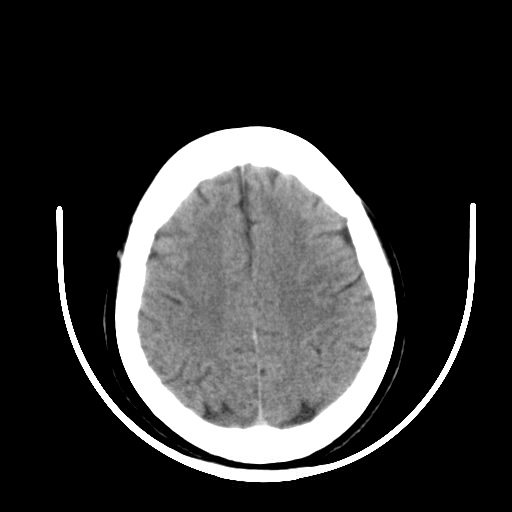

标题: CT16579:女 65岁间断性抽搐. [打印本页]

标题: CT16579:女 65岁间断性抽搐.

考虑右侧颞叶脑软化灶并脑穿通畸形;建议必要时行进一步检查。

右侧蛛网膜囊肿

右颞叶脑软化灶。余未见明显异常。

考虑右颞叶脑软化灶

右颞叶软化灶,右基底节区腔隙性脑梗塞;